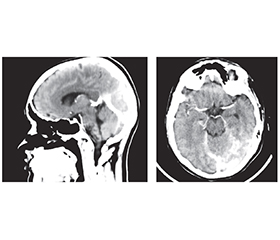

Церебральний венозний тромбоз є достатньо рідкісним типом порушення мозкового кровообігу і являє собою наявність тромбу у венозних синусах твердої оболонки й венах головного мозку. Церебральний венозний тромбоз найчастіше зустрічається у пацієнтів молодого віку, здебільшого у жінок. Фактори ризику церебральних венозних тромбозів можуть бути транзиторними або хронічними. До ключових належать статево-специфічні гормональні зміни: пероральна контрацепція і гормональна (переважно естрогенна) терапія, вагітність, інфекції, дегідратація, онкологічні, гематологічні й автоімунні захворювання. Найпоширеніший симптом тромбозу венозних синусів — інтенсивний головний біль, що є відображенням розвитку внутрішньочерепної гіпертензії; іншими симптомами можуть бути: фокальний неврологічний дефіцит, епілептичні напади, втрата або зміна свідомості до коми, порушення зору, менінгеальний синдром. Магнітно-резонансна томографія і магнітно-резонансна венографія є найбільш точними й високочутливими методами діагностики тромбозу церебральних венозних синусів, однак для підвищення вірогідності діагностики слід зважати і на результати інших методів дослідження, включно з комп’ютерною томографією і КТ-ангіографією. Тромби присутні у вигляді дефектів наповнення. Частота рецидивів тромбозів венозних синусів коливається від 1 до 4 % на рік, але вищий ризик може бути в осіб із тяжкою тромбофілією, включно зі злоякісними новоутвореннями. Лікування гострої стадії починається з парентерального введення низькомолекулярних гепаринів із подальшим переходом до пероральних антикоагулянтів протягом 3–12 місяців для посилення реканалізації та запобігання рецидиву. Жінкам із тромбозом церебральних венозних синусів у зв’язку із застосуванням комбінованих гормональних контрацептивів або вагітністю слід утримуватися від продовження або поновлення гормональної контрацепції через підвищений ризик рецидиву. Ми також наводимо клінічний випадок протяжного тромбозу верхнього сагітального синуса з поширенням тромбу в лівий поперечний, сигмоподібний синуси та внутрішню яремну вену у молодої жінки на тлі прийому гормональних естрогенвмісних препаратів зі сприятливим результатом.

Cerebral venous thrombosis is a fairly rare type of cerebral circulatory disorder; there is a thrombus in the venous sinuses of the dura mater and veins of the brain. Cerebral venous thrombosis is most common in young patients, more often in women. Risk factors for cerebral venous thrombosis can be transient or chronic. The key ones include sex-specific hormonal changes: oral contraception and hormonal (mainly estrogen) therapy, pregnancy, infections, dehydration, cancer, hematologic and autoimmune diseases. The most common symptom of venous sinus thrombosis is intense headache, which is a reflection of the development of intracranial hypertension; other symptoms may be focal neurological deficit, epileptic seizures, loss or change of consciousness up to coma, visual impairment, meningeal syndrome. Magnetic resonance imaging and magnetic resonance venography are the most accurate and highly sensitive methods for diagnosing cerebral venous sinus thrombosis, but to increase the reliability of the diagnosis, the results of using other research methods should be taken into account such as computed tomography and computed tomography angiography. Thrombi are present in the form of filling defects. The recurrence rate of venous sinus thrombosis ranges from 1 to 4 % per year, but the risk may be higher in individuals with severe thrombophilia, as well as malignant neoplasms. Treatment of the acute phase begins with parenteral administration of low-molecular-weight heparins followed by a transition to oral anticoagulants for 3–12 months to enhance recanalization and prevent recurrence. Women with cerebral venous sinus thrombosis resulting from the use of combined hormonal contraceptives or pregnancy should refrain from continuing or resuming hormonal contraception due to an increased risk of recurrence. We also present a clinical case of extensive superior sagittal sinus thrombosis with the spread of the thrombus to the left transverse, sigmoid sinuses and internal jugular vein in a young woman on the background of taking hormonal estrogen-containing drugs, with a favorable outcome.